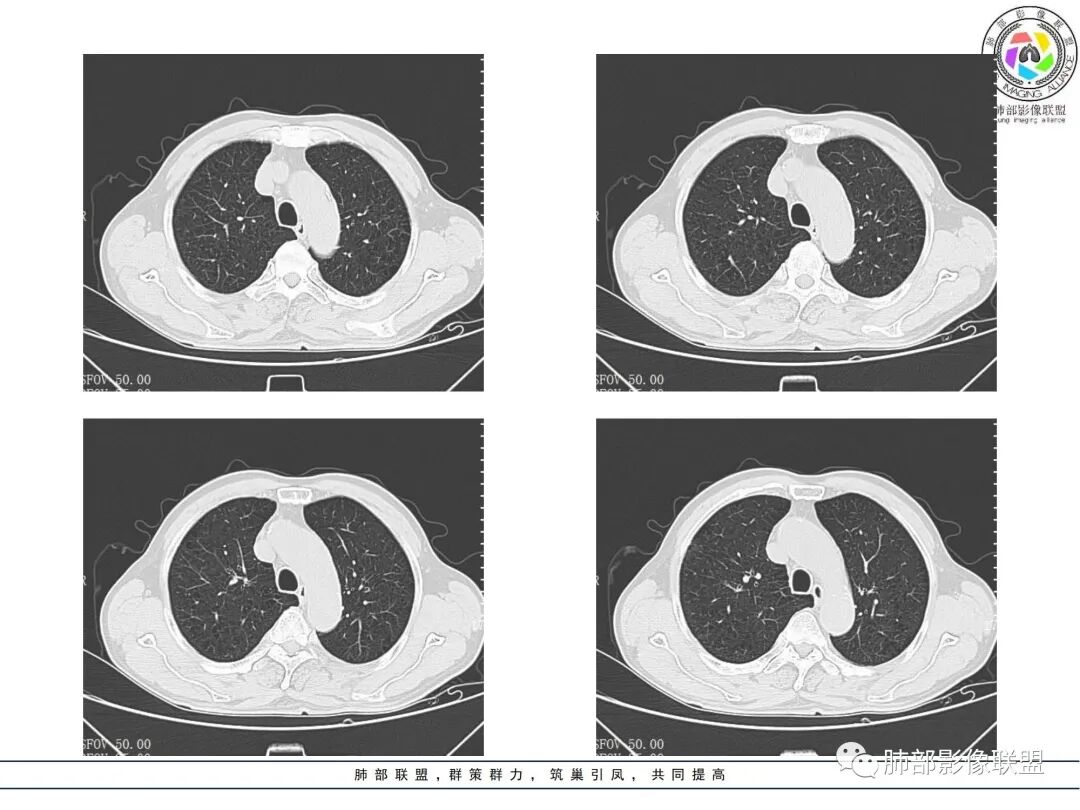

右肺上叶实变,宽基底与胸膜相连,邻近胸膜积液,上叶支气管阻塞,不均匀强化,血管显示可,局部坏死环形强化,可见气泡,考虑慢性炎症伴脓肿,放线菌?鉴别腺癌

右肺上叶尖段大片状实变,近肺门侧支气管闭塞,并可见病灶内部有片状液化坏死区,有空泡气体,病灶紧贴胸膜,胸膜反应性增厚,伴有少见积液,增强扫描内部不均匀强化,血管走形正常。影像符合慢性化脓性感染。

右肺上叶大片实变影,内密度不均匀,可见坏死环形强化,支气管被粘液栓阻塞,首先考虑感染性病变,奴卡?放线菌感染?

右肺上叶大片实变,密度不均,中度不均匀强化,有坏死、支气管粘液栓,病灶边缘清楚,无胸膜下栽赃,考虑炎性,临床病程长,无发热,血项也不支持普通炎症,考虑特殊感染,TB?曲霉?放线菌?

右肺上叶大片实变,密度不均,近端环形强化并见空泡,病灶与胸膜广基相连,之间并可见积液,考虑放线菌,鉴别腺癌

晨读:右肺上叶实变,密度欠均匀,不均匀强化,内血管走形可,近端环形强化并见空泡,考虑放线菌可能,鉴别腺癌

右肺上叶实变,宽基底与胸膜相连,不均匀强化,血管显示可,局部坏死环形强化,可见气泡,考虑慢性炎症伴脓肿,放线菌?鉴别腺癌

右主支气管周围多发淋巴结肿大融合(提示右主支气管有外受压变窄),右肺上叶尖前不张,内见支气管粘液栓和坏死及环形强化特点,邻近胸膜增厚及右肺上叶后段支气管扭曲及狭窄后扩张,周边索条纤维化,综合TB表现,超声支气管镜检查。

凝固性坏死,肉芽肿性炎症,放线菌可能

老年女性患者胸痛咳嗽半年多时间。右肺上叶大片状实性病灶,近端支气管受压变窄。病灶内部密度不均,伴有不均匀强化,有局灶坏死,以及有支气管造影征,胸膜面显示不行,伴有少量的积液,病灶有局部的膨胀,纵隔淋巴结增大。

病灶的主要特点支气管变窄,病灶内及淋巴结有血管的漂浮。淋巴瘤及腺癌的可能性大。鉴别诊断:奴卡或TB?

老年女性患者胸痛咳嗽半年多时间。右肺上叶大片状实性病灶,近端支气管受压变窄。病灶内部密度不均,伴有不均匀强化,有局灶坏死,以及有支气管造影征,胸膜面显示不清,伴有少量的积液,病灶有局部的膨胀,纵隔淋巴结增大。

晨读,中年女性,咳嗽半年,右肺上叶斑片影,可见坏死及环形强化,血管影走形自然,胸膜增厚积液,纵隔淋巴结增大,右肺上叶支气管阻塞,考虑慢性炎症伴局部脓肿形成,鉴别腺癌?淋巴瘤?

中年女性,咳嗽,咳痰半年,CRP升高,右肺上叶大片实变,密度不均匀,边缘部见类圆形低密度影,内夹杂气体影,增强后呈环形强化,病变内血管走形征象,边缘略毛糙,考虑①炎性伴脓肿形成②上叶支气管截断,恶性不除外,鳞癌?

右肺门结节,显著强化,内可见坏死及悬浮气泡,远端阻塞性肺不张,心脏纵隔右移,结节及不张内血管影走行自然,并可见粘液拴,隆突下淋巴结肿大,慢性病程,病变跨叶,首选感染性病变放线菌感染,其次鉴别腺癌

晨读:右肺上叶大片状实变影,血管走形自然,可见类圆形低密度区,其内可见气泡影,纵膈内可见肿大淋巴结显示。考虑慢性炎症并脓肿形成,放线菌可能。鉴别淋巴瘤、腺癌。

有脓腔,内壁光滑、强化环——支持感染

远端是不张合并感染

右肺上叶后段支气管狭窄后扩张,周边纤维化,TB特点之一。

右肺大片状高密度灶,密度不均,近端支气管堵塞,强化结节,远端气管粘液栓,考虑恶性,粘液表皮样癌?